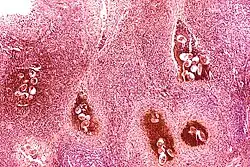

Granulomas

La reacción del sistema inmune a los huevos depositados en los tejidos produce granulomas, los cuales son cubiertas inmunitarias (celular y fibróticas) alrededor del huevo que se tornan cicatrizantes. Estos granulomas pueden ocurrir en cualquier órgano del cuerpo. Esta patología característica del S. mansoni y de S. japonicum producen las llamadas Fiebre de Katayama, con fibrosis periportal, hipertensión portal, y ocasionalmente embolias producidas por granulomas cerebrales o espinales. La fibrosis alrededor de los vasos porta intrahepáticos se denomina en medicina Fibrosis de Symmer o en tallo de pipa.

La infección continuada puede causar reacciones granulomatosas y fibrosis en los órganos afectados: